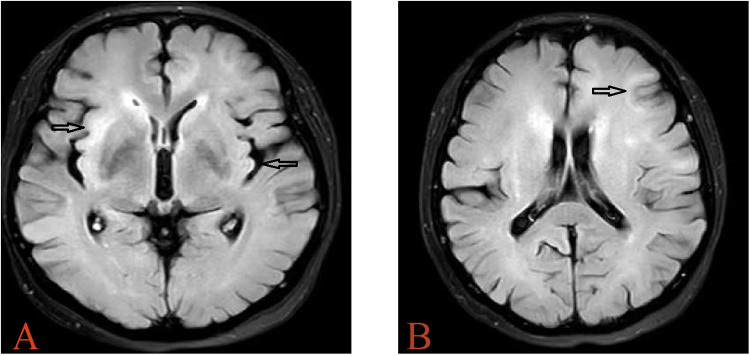

In this report, the patient was a 57-year-old woman who had been diagnosed with aplastic anemia for 3 years. This patient underwent allogeneic hematopoietic stem cell transplantation (allo-HSCT). Twenty-four months after allo-HSCT, the patient experienced cognitive dysfunction, memory loss, and involuntary movements. Various central nervous system (CNS) complications may occur after allo-HSCT, which can lead to severe clinical problems. Diagnosis is often difficult because of the absence of distinctive clinical symptoms. In addition, different neurological disorders may show similar symptoms. Although antibodies in the CSF or serum have become well recognized in several CNS disorders, cases of autoimmune CNS disorders after allo-HSCT have rarely been reported. Here, we report the case of a patient who developed encephalitis associated with antibodies against glial fibrillary acidic protein (GFAP) after allo-HSCT. To the best of our knowledge, this is the first report of the involvement of antibodies against GFAP in post-transplantation encephalitis. Of course, all processes met the ethical and patient consents were obtained.